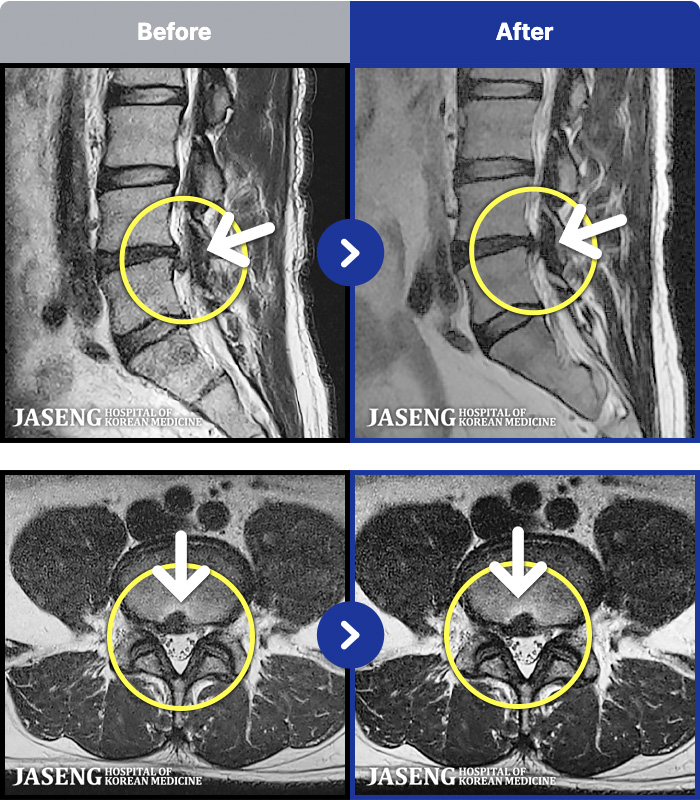

[] 23.11.11~25.06.04